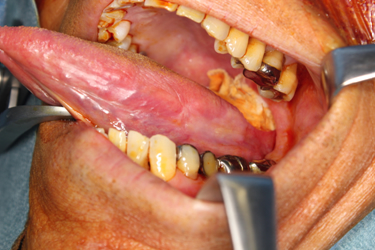

• 骨髄炎に対する治療骨髄炎に対する治療 顎骨骨髄炎 顎骨骨髄炎とは、口腔内細菌の感染に起因する炎症が顎骨内の骨髄にまで波及することで様々な症状を惹起し、時にとても治療が困難となる疾患です。 健康な方であっても、う蝕(むし...> 続きを見る